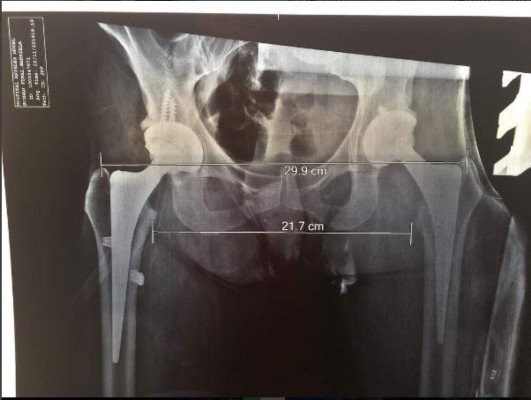

En esta última operación la intérprete de “Un día de suerte” publicó un video y fotografías del implante de titanio que le fue puesto en su cadera.